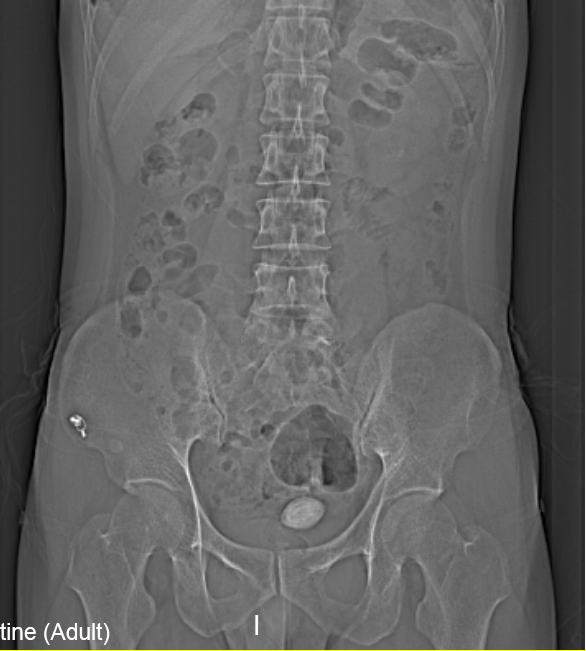

“醫(yī)生我尿不出,尿里有血,快幫幫我”。近日,在溫州市人民醫(yī)院泌尿外科門診一位男青年向坐診的黃來劍主任求助,經(jīng)驗豐富的黃主任在了解基本病情后,特意觸摸了一下患者恥骨上區(qū),并囑咐患者進行泌尿系平片檢查,結(jié)果在意料之中也出乎意料之外。意料之中的是患者診斷如黃主任所想膀胱結(jié)石進入尿道卡住了,意料之外的是結(jié)石直徑達到了35mm,像蛋黃大小了,這對年輕患者來說并不常見,堵住了尿道,把患者痛的夠嗆。

▲患者影像學檢查